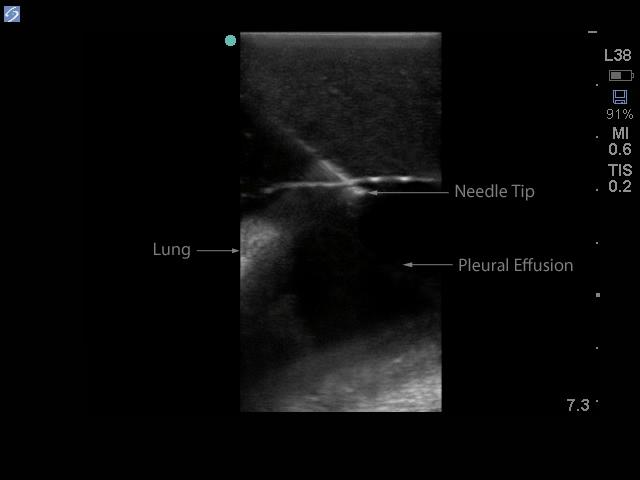

The model is of a supine adult male and extends from the upper buttocks to the lower neck. Positioned in the mid scapulary line, the ultrasound tissue insert contains chest wall superficial tissue, 6th, 7th, 8th, and 9th ribs and intercostal spaces, pleural cavity with lung and atelectatic lung, diaphragm, and superior spleen. The pleural fluid collections allow users to develop and refine their ultrasound guided thoracentesis skills. This model is extremely realistic and is self-healing offering you superb training with a low cost of ownership.

The ultrasound tissue insert offers extremely realistic sonographic imaging characteristics is designed for guiding the placement of needles and small catheters (18-21 gauge and associated catheter kits). Blue Phantom simulated human tissue is very realistic and ultra-durable; excellent for repeated training in skills associated with ultrasound guided thoracentesis procedures. Positive fluid flow offers users feedback when pleural effusions are accurately accessed. The fluid is easily refilled using a quick fill luer lock or can be connected to an I.V. reservoir for continuous fluid delivery. Users can also learn to avoid accessory structures as the spleen, diaphragm and lung.

Ultrasound imaging skills include; using ultrasound system controls, transducer positioning and movement, recognition of thoracic anatomy, lung, diaphragm, anterior spleen and pleural effusions, using ultrasound to target the appropriate fluid pockets for needle guidance, and performing an ultrasound guided thoracentesis procedure. Our self-healing tissue will allow you to repeatedly perform ultrasound guided thoracentesis procedures without giving second thought to wearing out the tissue or calculating the cost per cannulation. You can expect unmatched durability from our tissue. This ultrasound training mannequin is constructed using Blue Phantom’s patented ultra-durable tissue and is extremely realistic in ultrasound imaging characteristics and feels like real human tissue. Our self-healing tissue will withstand tremendous use and will save you money by dramatically reducing the necessity for purchasing replacement parts. Constructed using Blue Phantom simulated tissue which match the acoustic characteristics of real human tissue so when you use your ultrasound system on our training models, you experience the same quality you expect from imaging patients in a clinical environment.

Blue Phantom's mid-scapular thoracentesis ultrasound training model is specifically designed for ultrasound guided thoracentesis procedures. This ultrasound training phantom aids users in developing and practicing the skills associated with a mid scapulary approach to ultrasound guided thoracentesis procedures. This model is excellent for assisting clinicians in gaining proficiency in using ultrasound to identify and guide needle and small gauge catheter insertions in a patient with pleural effusions for diagnostic and/or therapeutic purposes.The model is of a supine adult male and extends from the upper buttocks to the lower neck. Positioned in the mid scapulary line, the ultrasound tissue insert contains chest wall superficial tissue, 6th, 7th, 8th, and 9th ribs and intercostal spaces, pleural cavity with lung and atelectatic lung, diaphragm, and superior spleen. The pleural fluid collections allow users to develop and refine their ultrasound guided thoracentesis skills. This model is extremely realistic and is self-healing offering you superb training with a low cost of ownership.

The ultrasound tissue insert offers extremely realistic sonographic imaging characteristics is designed for guiding the placement of needles and small catheters (18-21 gauge and associated catheter kits). Blue Phantom simulated human tissue is very realistic and ultra-durable; excellent for repeated training in skills associated with ultrasound guided thoracentesis procedures. Positive fluid flow offers users feedback when pleural effusions are accurately accessed. The fluid is easily refilled using a quick fill luer lock or can be connected to an I.V. reservoir for continuous fluid delivery. Users can also learn to avoid accessory structures as the spleen, diaphragm and lung.

Ultrasound imaging skills include; using ultrasound system controls, transducer positioning and movement, recognition of thoracic anatomy, lung, diaphragm, anterior spleen and pleural effusions, using ultrasound to target the appropriate fluid pockets for needle guidance, and performing an ultrasound guided thoracentesis procedure. Our self-healing tissue will allow you to repeatedly perform ultrasound guided thoracentesis procedures without giving second thought to wearing out the tissue or calculating the cost per cannulation. You can expect unmatched durability from our tissue. This ultrasound training mannequin is constructed using Blue Phantom’s patented ultra-durable tissue and is extremely realistic in ultrasound imaging characteristics and feels like real human tissue. Our self-healing tissue will withstand tremendous use and will save you money by dramatically reducing the necessity for purchasing replacement parts. Constructed using Blue Phantom simulated tissue which match the acoustic characteristics of real human tissue so when you use your ultrasound system on our training models, you experience the same quality you expect from imaging patients in a clinical environment.

- Ultrasound tissue module contains the chest wall superficial tissue, 6th, 7th, 8th, and 9th ribs and intercostal spaces, pleural cavity with lung and atelectatic lung, diaphragm, and superior spleen.

- Superb ultrasound imaging characteristics: extremely realistic in ultrasound imaging characteristics and feels like real human tissue

- Ultrasound tissues match the acoustic characteristics of real human tissue so when you use your ultrasound system on our training models, you experience the same quality you expect from imaging patients in a clinical environment